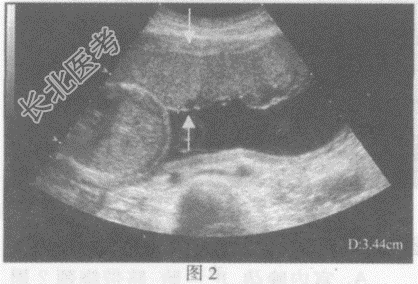

- 单项选择题请指出下图箭头间所指的是宫内妊娠哪个部位:

A、图1:胎盘厚度,图2:羊水深度

B、图1:羊水深度,图2:胎盘厚度

C、图1:胎儿双顶径,图2:胎儿腹围

D、图1:胎儿股骨长径,图2:胎儿股骨长径

E、图1:胎儿腹围,图2:胎儿双顶径